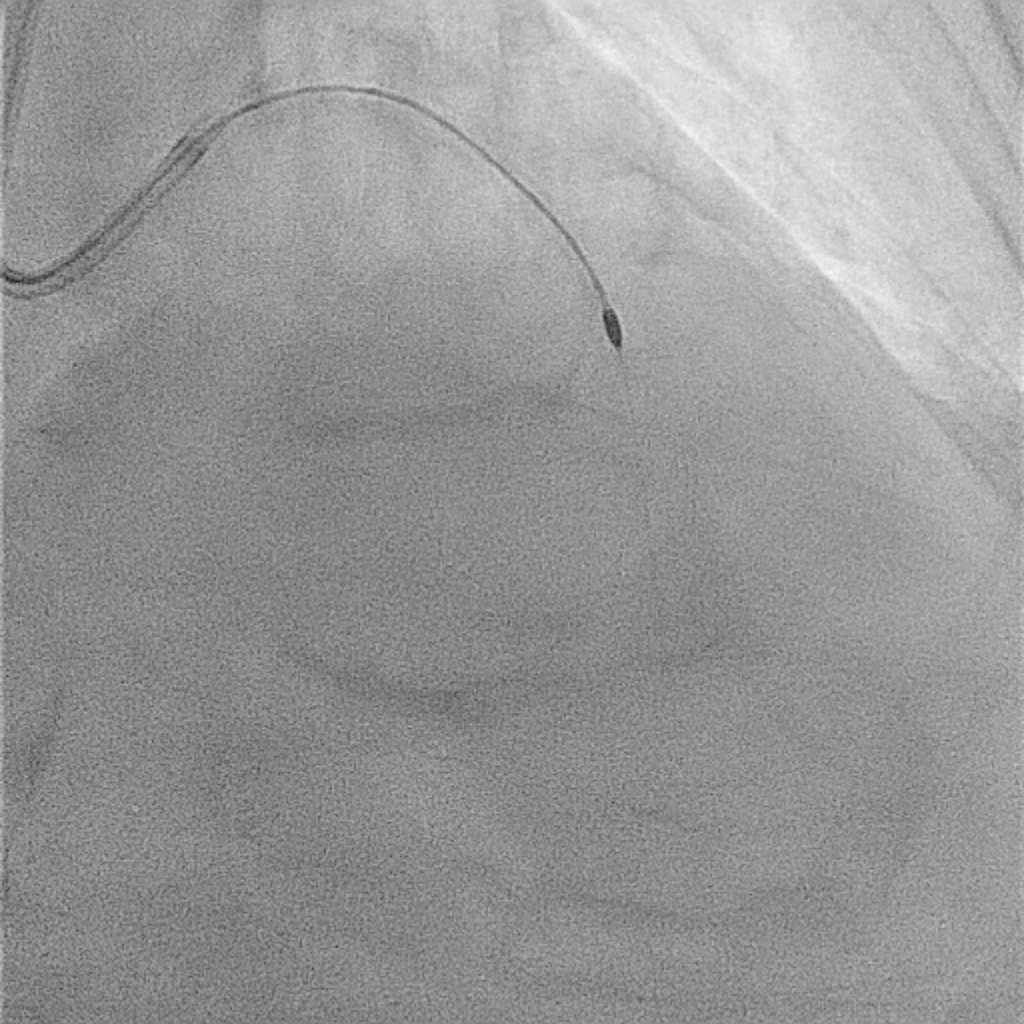

1. Prophylactic mechanical circulatory support with extracorporeal membrane oxygenation (ECMO) was initiated in response to a complex high-risk PCI case that had a high BCIS Jeopardy Score of 12 points.2. Arterial access was obtained via the right femoral artery. A 7 Fr EBU 3.5 guiding catheter was used for the left coronary system, and a 6 Fr JR 3.5 catheter for the right.3. Intravascular ultrasound (IVUS) evaluation revealed long, circumferential calcification with a small luminal area in the LAD (MLA= 2.43mm2), and a prominent calcium nodule extending from the left main to the LCx (MLA= 2.52mm2).4. Owing to severe calcification and an undilatable lesion in the LAD, rotational atherectomy from the proximal to mid segment was performed using a 1.25-mm burr, followed by cutting balloon angioplasty.5. Intravascular lithotripsy (IVL, 3.0 mm) was performed on the proximal LCx and left main bifurcation, combined with cutting balloon angioplasty.6. Double-kissing (DK) crush stenting technique was applied at the left main bifurcation for complex lesion management.7. Finally, three drug-eluting stents (DES) were implanted in the LAD, one in the LCx, and one in the RCA.